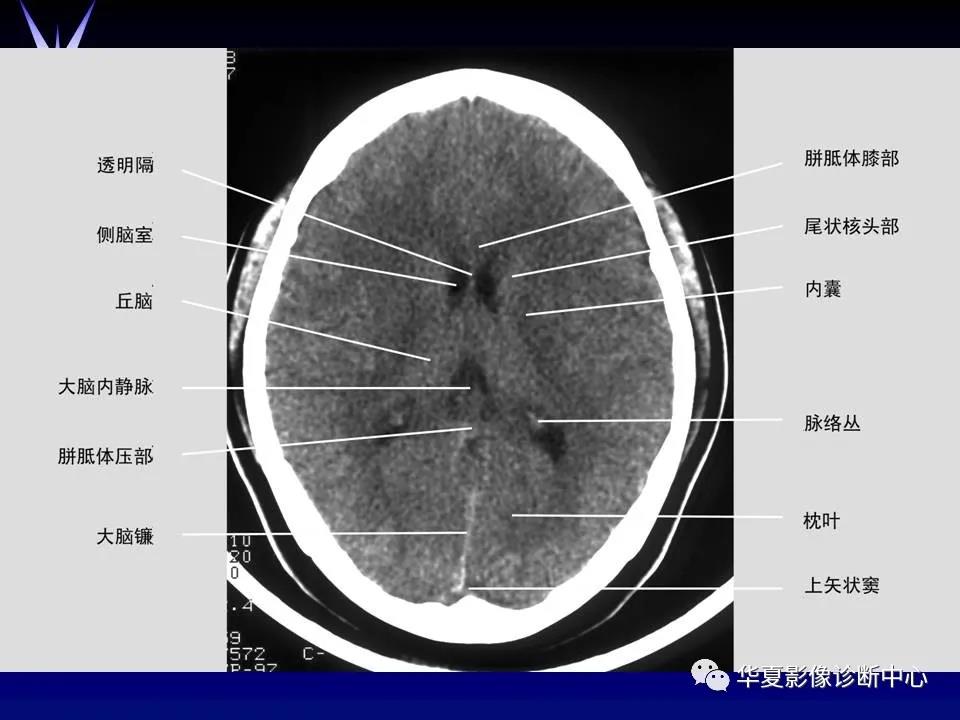

来源:华夏影像诊断中心